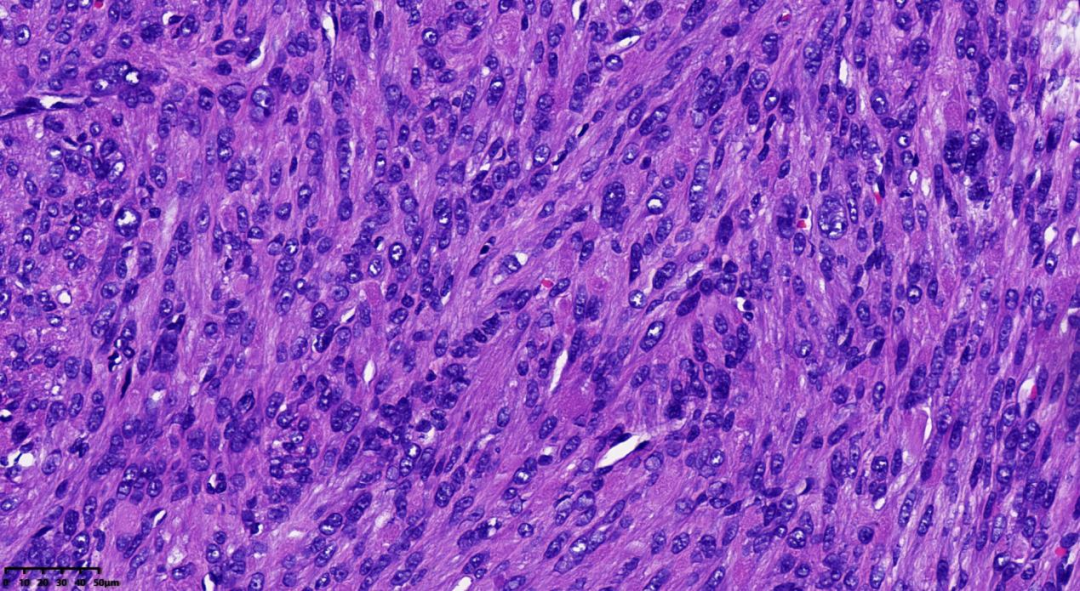

细胞丰富,链状排列的卵圆形核,核异型,见嗜酸性核仁

链状排列的卵圆形核,可见奇异性核;嗜酸性核仁,可见核仁周围空晕

肿瘤细胞密度相对较高;间质内常出现鹿角样血管;由于间质常伴有水肿,故形成肺泡样水肿结构;散在分布奇异型细胞及多核细胞;细胞核呈卵圆形;细胞核有时出现链状排列;可见胞质内嗜酸性小体;细胞核中可见突出的嗜酸性核仁,且核仁周围可见空晕。

常为轻度的核不典型性,核分裂象<5/10HPF。